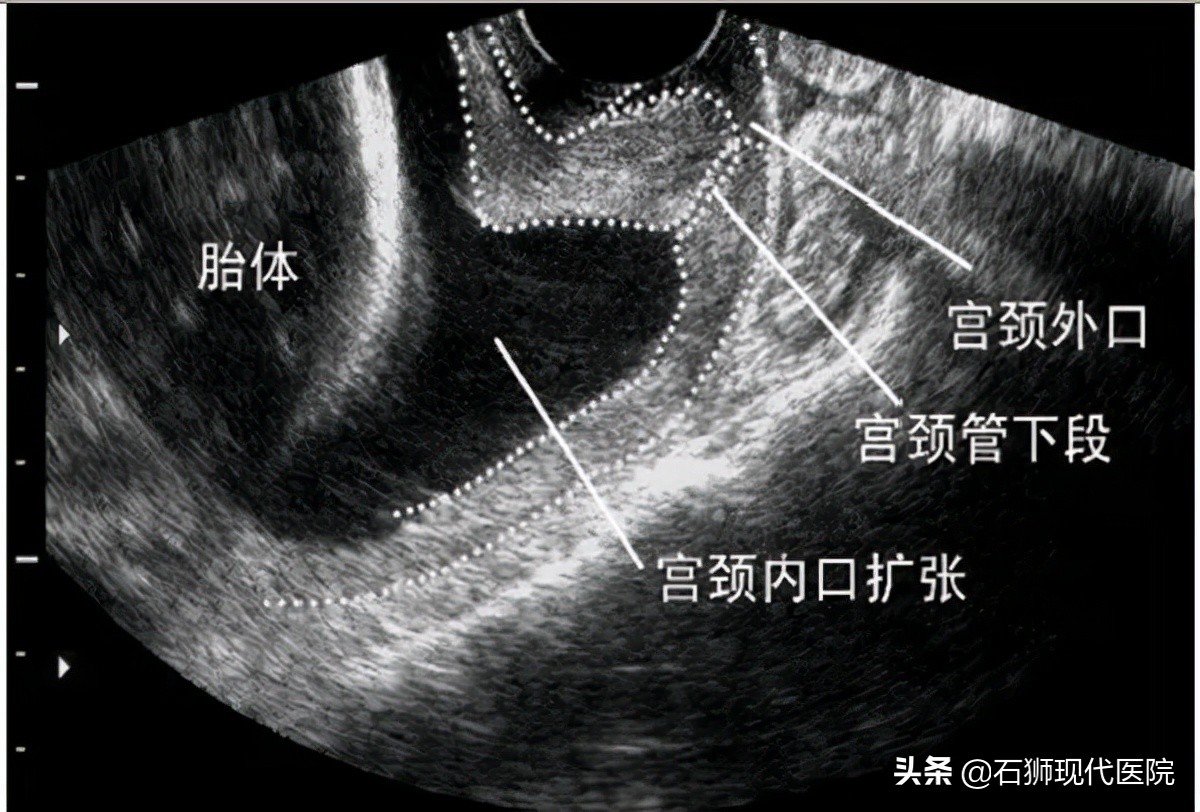

一般来说,宫颈内口是闭合的,直至分娩前,宫颈口才打开。但宫颈机能不全的患者,宫颈口呈U形,通俗一点讲,就像一个口袋没有扎紧一样。随着胎儿越长越大,子宫兜不住,就以流产告终了。

宫颈环扎术就是在宫颈内口水平环扎子宫颈,使之关闭,把宫颈口像面粉袋口一样用绳子系起来,这样就可以让宝宝继续生长。